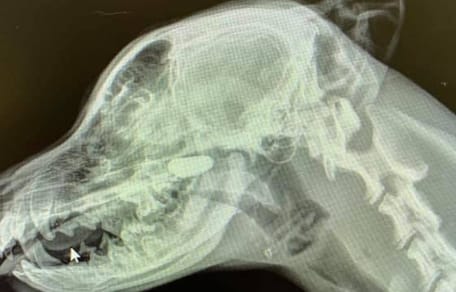

Zdjęcie rentgenowskie głowy psa

Widok zdjęcia rentgenowskiego wprawił wszystkich w osłupienie

© Sarah Yuki @Iloveveterinarymedicine / Facebook

Lekarka kontynuowała więc badania i zleciła wykonanie zdjęć rentgenowskich młodego psa. Najpierw klatki piersiowej, ale na tym zdjęciu Sara przy najlepszych chęciach nie mogła dostrzec niczego podejrzanego. Dlatego zleciła jeszcze prześwietlenie głowy i szyi z boku. I to okazało się strzałem w dziesiątkę!

W nosogardzieli wyraźnie widać ciało obce, którego absolutnie nie powinno tam być.

Okazało się, że to kamień, który szczeniak w jakiś sposób włożył sobie do nosa! Po jego usunięciu szczeniakowi od razu się poprawiło.